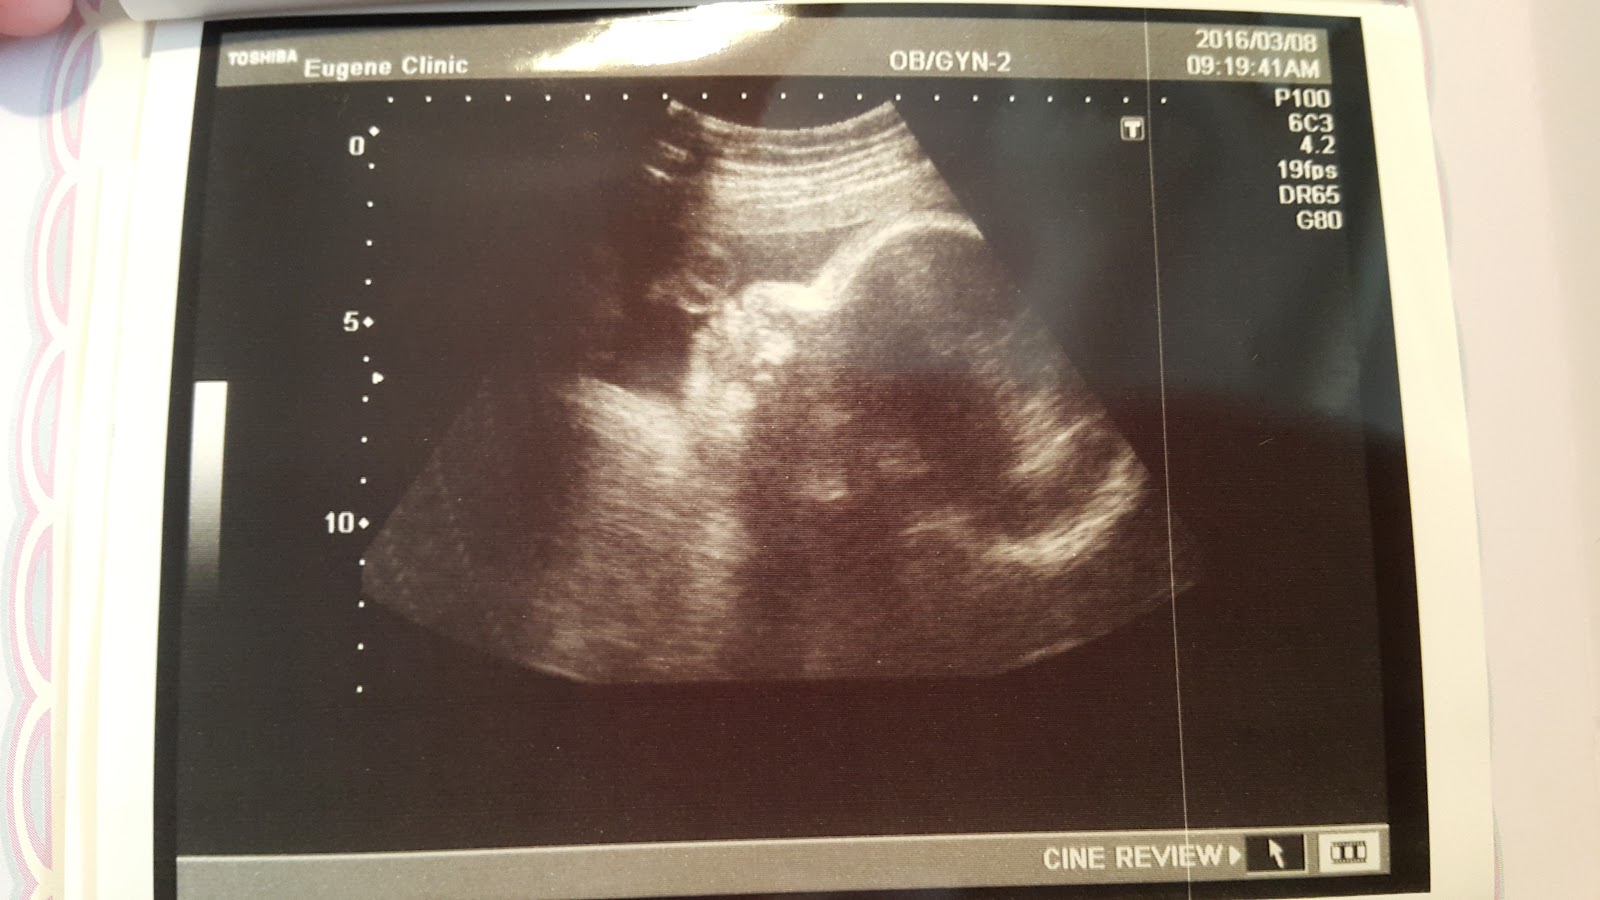

目前Haru的體重來到2140g,2週前還是1780g

側臉照依舊很cute~

現在位置已經是頭下腳上,安穩的卡好位置